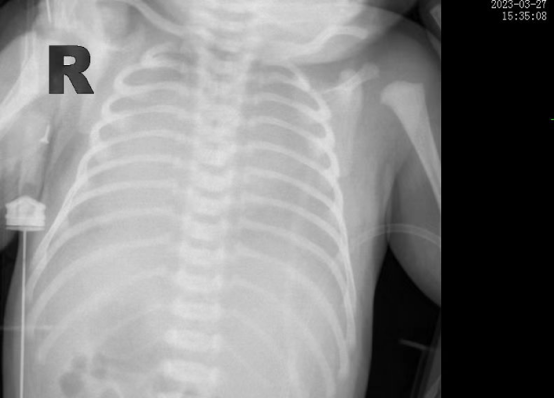

時間追溯到3月27日����,該患兒出生時哭聲欠連貫����,全身可見黃色胎糞附著,羊水三度污染��,呼吸稍促����,血氧飽和度低,立即被轉(zhuǎn)入新生兒科���。醫(yī)生立即予以清理呼吸道�����,常壓給氧�,建立靜脈通道后抱入暖箱復溫,同時以無創(chuàng)輔助通氣���。然而患兒呼吸窘迫癥狀正在進行性加重���,胸片提示“白肺”��,結合血氣分析等檢查后���,患兒被診斷為“急性呼吸窘迫綜合癥”��、“呼吸衰竭”��。時間就是生命�����,主管醫(yī)生張海嬌在與家屬充分溝通同時���,副主任醫(yī)師鐘玉芬立即帶領新生兒醫(yī)護團隊快速采取急救措施��,給予患兒氣管插管術進行有創(chuàng)呼吸機高頻震蕩通氣,并從氣管內(nèi)滴入PS(肺表面活性物質(zhì))��,以降低肺泡表面張力����,增加肺順應性���,患兒血氧這才穩(wěn)定下來����。

在科室團隊的共同努力下,患兒歷經(jīng)5天有創(chuàng)通氣5天無創(chuàng)通氣��,再調(diào)整為5天吸氧后已經(jīng)實現(xiàn)呼吸自由��,復查肺部CT,終于看到白肺已云開霧散�����。4月15日����,歷時17天的醫(yī)療救治,患兒順利出院�����,回到了媽媽的懷抱�����。